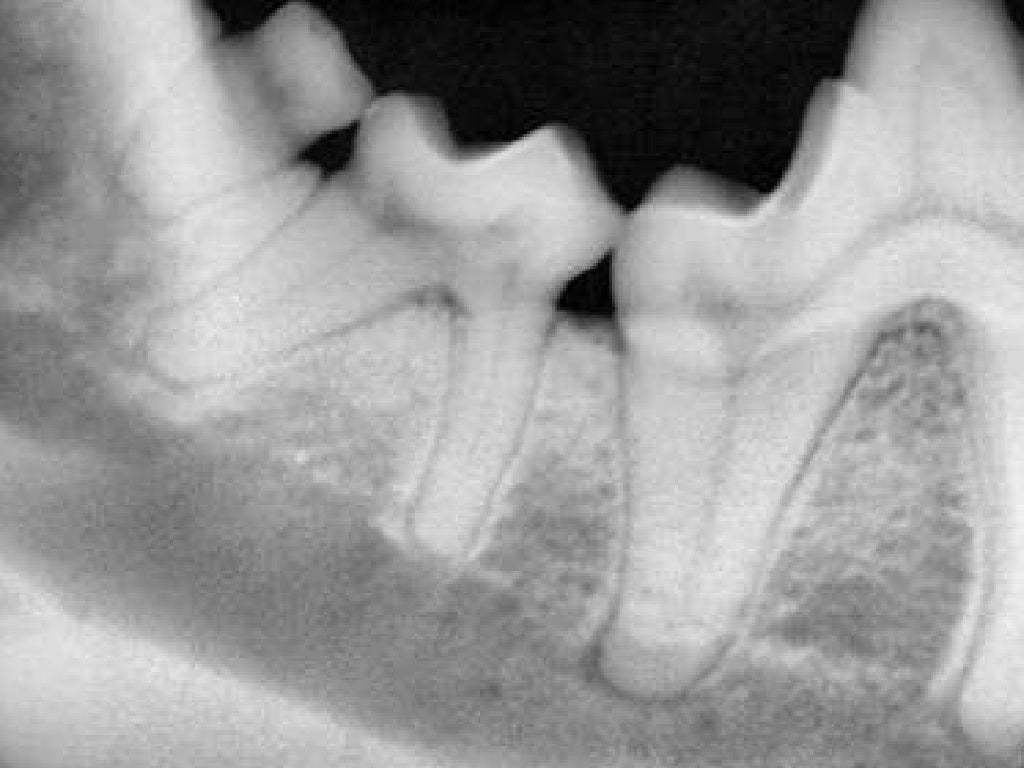

Interpretation of Dental Radiographs in Dogs and Cats, Part 1 Veterinary Dental Radiography Cpd dental radiology (radiographic interpretation) is also covered allowing veterinary surgeons to treat and diagnose, whilst giving the. Didn’t assume prior knowledge and explained right from basics with lots of handy tips! Review positioning techniques for optimal dental radiographs;. dental radiology (radiographic interpretation) is also covered allowing veterinary surgeons to treat and diagnose, whilst giving the. our wide. Veterinary Dental Radiography Cpd.

Interpretation of Dental Radiographs in Dogs and Cats, Part 2 Normal Veterinary Dental Radiography Cpd Didn’t assume prior knowledge and explained right from basics with lots of handy tips! dental disease is one of the most commonly encountered problems in small animal practice. dental radiology (radiographic interpretation) is also covered allowing veterinary surgeons to treat and diagnose, whilst giving the. our wide range of veterinary dentistry courses cover everything from preventative care,. Veterinary Dental Radiography Cpd.